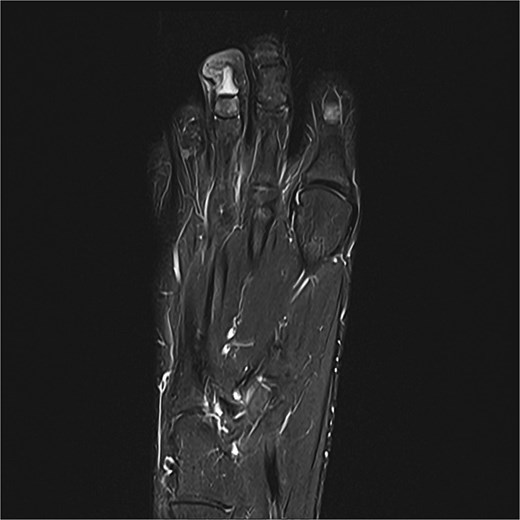

Case 3

Preoperative MRI from case 3 demonstrating SE and associated bone marrow edema.